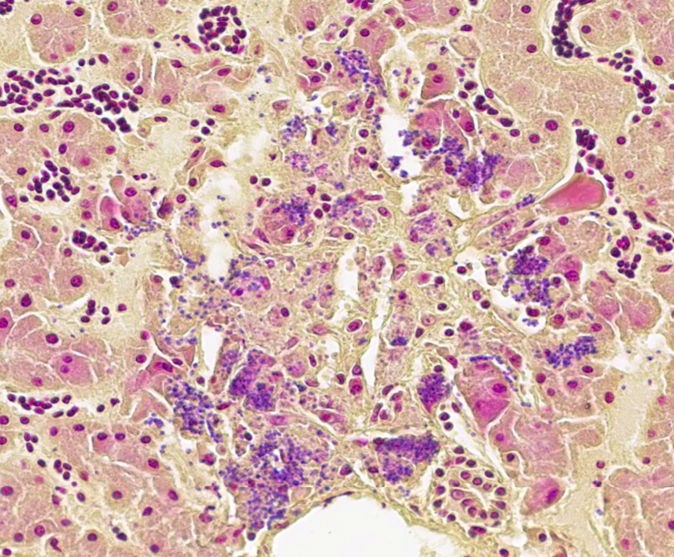

- Liver: Hepatitis, necrotizing, acute, multifocal, random, moderate with microbes consistent with microsporidia.

The liver had multifocal, random hepatocellular necrosis centered on microbes that were intracellular (within hepatocytes), round to ovoid, and 1.5-2.5µm with an eccentric clearing. These organisms were gram-positive, argyrophilic on GMS, and positively staining on Giemsa; PAS and acid-fast stains were negative. Conference participants discussed at length the potential identity of these organisms. The primary differential is Encephalitozoon hellum, which is a microsporidian parasite in psittacines. E. hellum is an intracellular parasite that is ovoid, 1.5-2.5 µm, and has a predilection for the liver.5 It is most common in immunosuppressed animals, which was likely in this case given the herpesvirus infection. Other differentials raised by participants included chlamydiosis, which can cause intra-cellular bacterial inclusions in the liver, but the individualized organisms were too large for chlamydiosis. Additionally, Chlamydia spp. would be expected to be gram-negative (unlike the gram-positive organisms in this case).5 Candidiasis was also considered; how-ever, yeasts should be positive for PAS (unlike the PAS negative organisms in this case) and is typically larger than 1.5µm.5 Ultimately, confirmatory diagnosis of E. hellum would require molecular investigation or ultrastructural analysis (transmission electron microscopy) revealing polar filaments.5

Participants also noted the characteristic “freeze-thaw” artifact of the liver that is best appreciated at low magnification and causes acicular clefts filled with pale eosinophilic fluid. This is a classic artifact to be aware of!